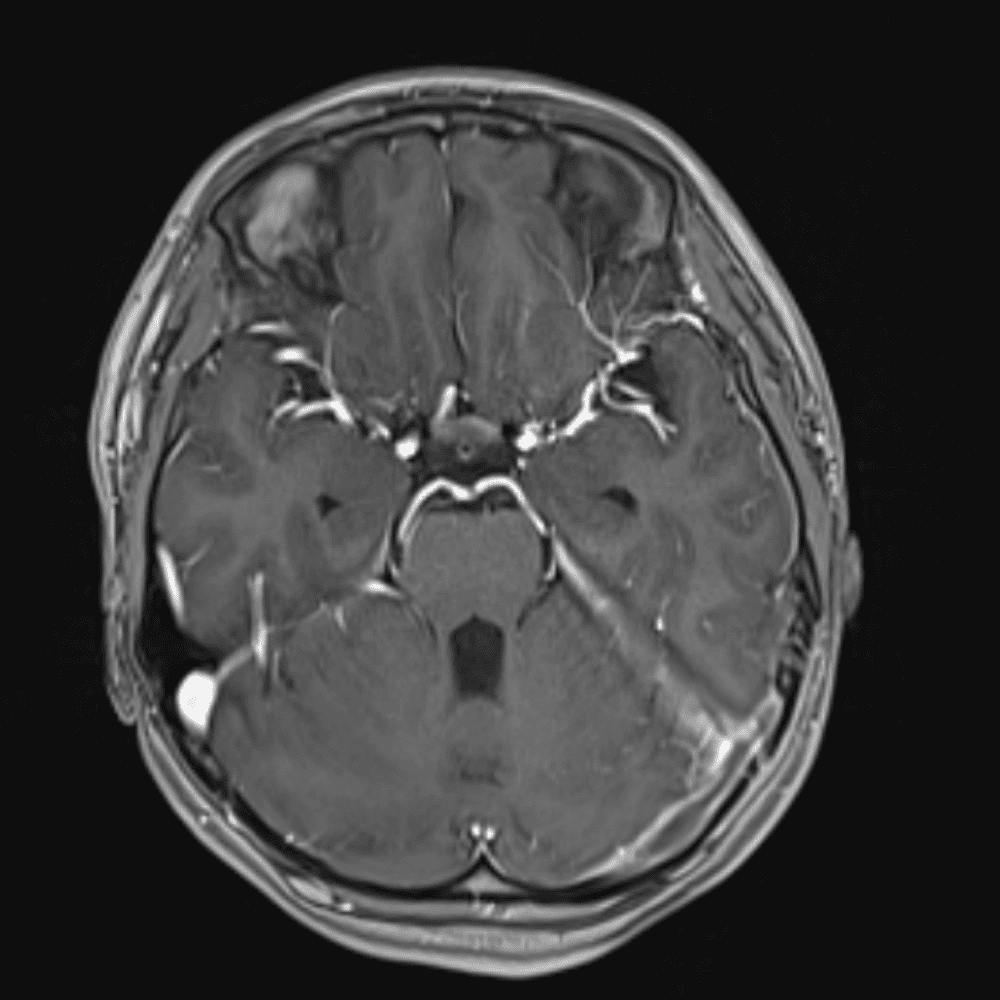

๋‹น์ง ์‹œ ํ”ํžˆ ๋ณผ ์ˆ˜ ์žˆ๋Š” ์‚ฌ๋ก€์˜ ์ „ํ˜•์ ์ธ ์˜ˆ๋ฅผ ํฌํ•จํ•ฉ๋‹ˆ๋‹ค.

39 ์‚ฌ๋ก€

์—ฐ์Šต

๋ฏธ๋ฌ˜ํ•˜๊ฑฐ๋‚˜ ์–ด๋ ค์šด ์‚ฌ๋ก€์™€ ์ผ๋ถ€ ์ •์ƒ ์‚ฌ๋ก€๋ฅผ ํฌํ•จํ•˜์—ฌ ๋‹น์ง์„ ์‹œ๋ฎฌ๋ ˆ์ด์…˜ํ•ฉ๋‹ˆ๋‹ค.

50 ์‚ฌ๋ก€